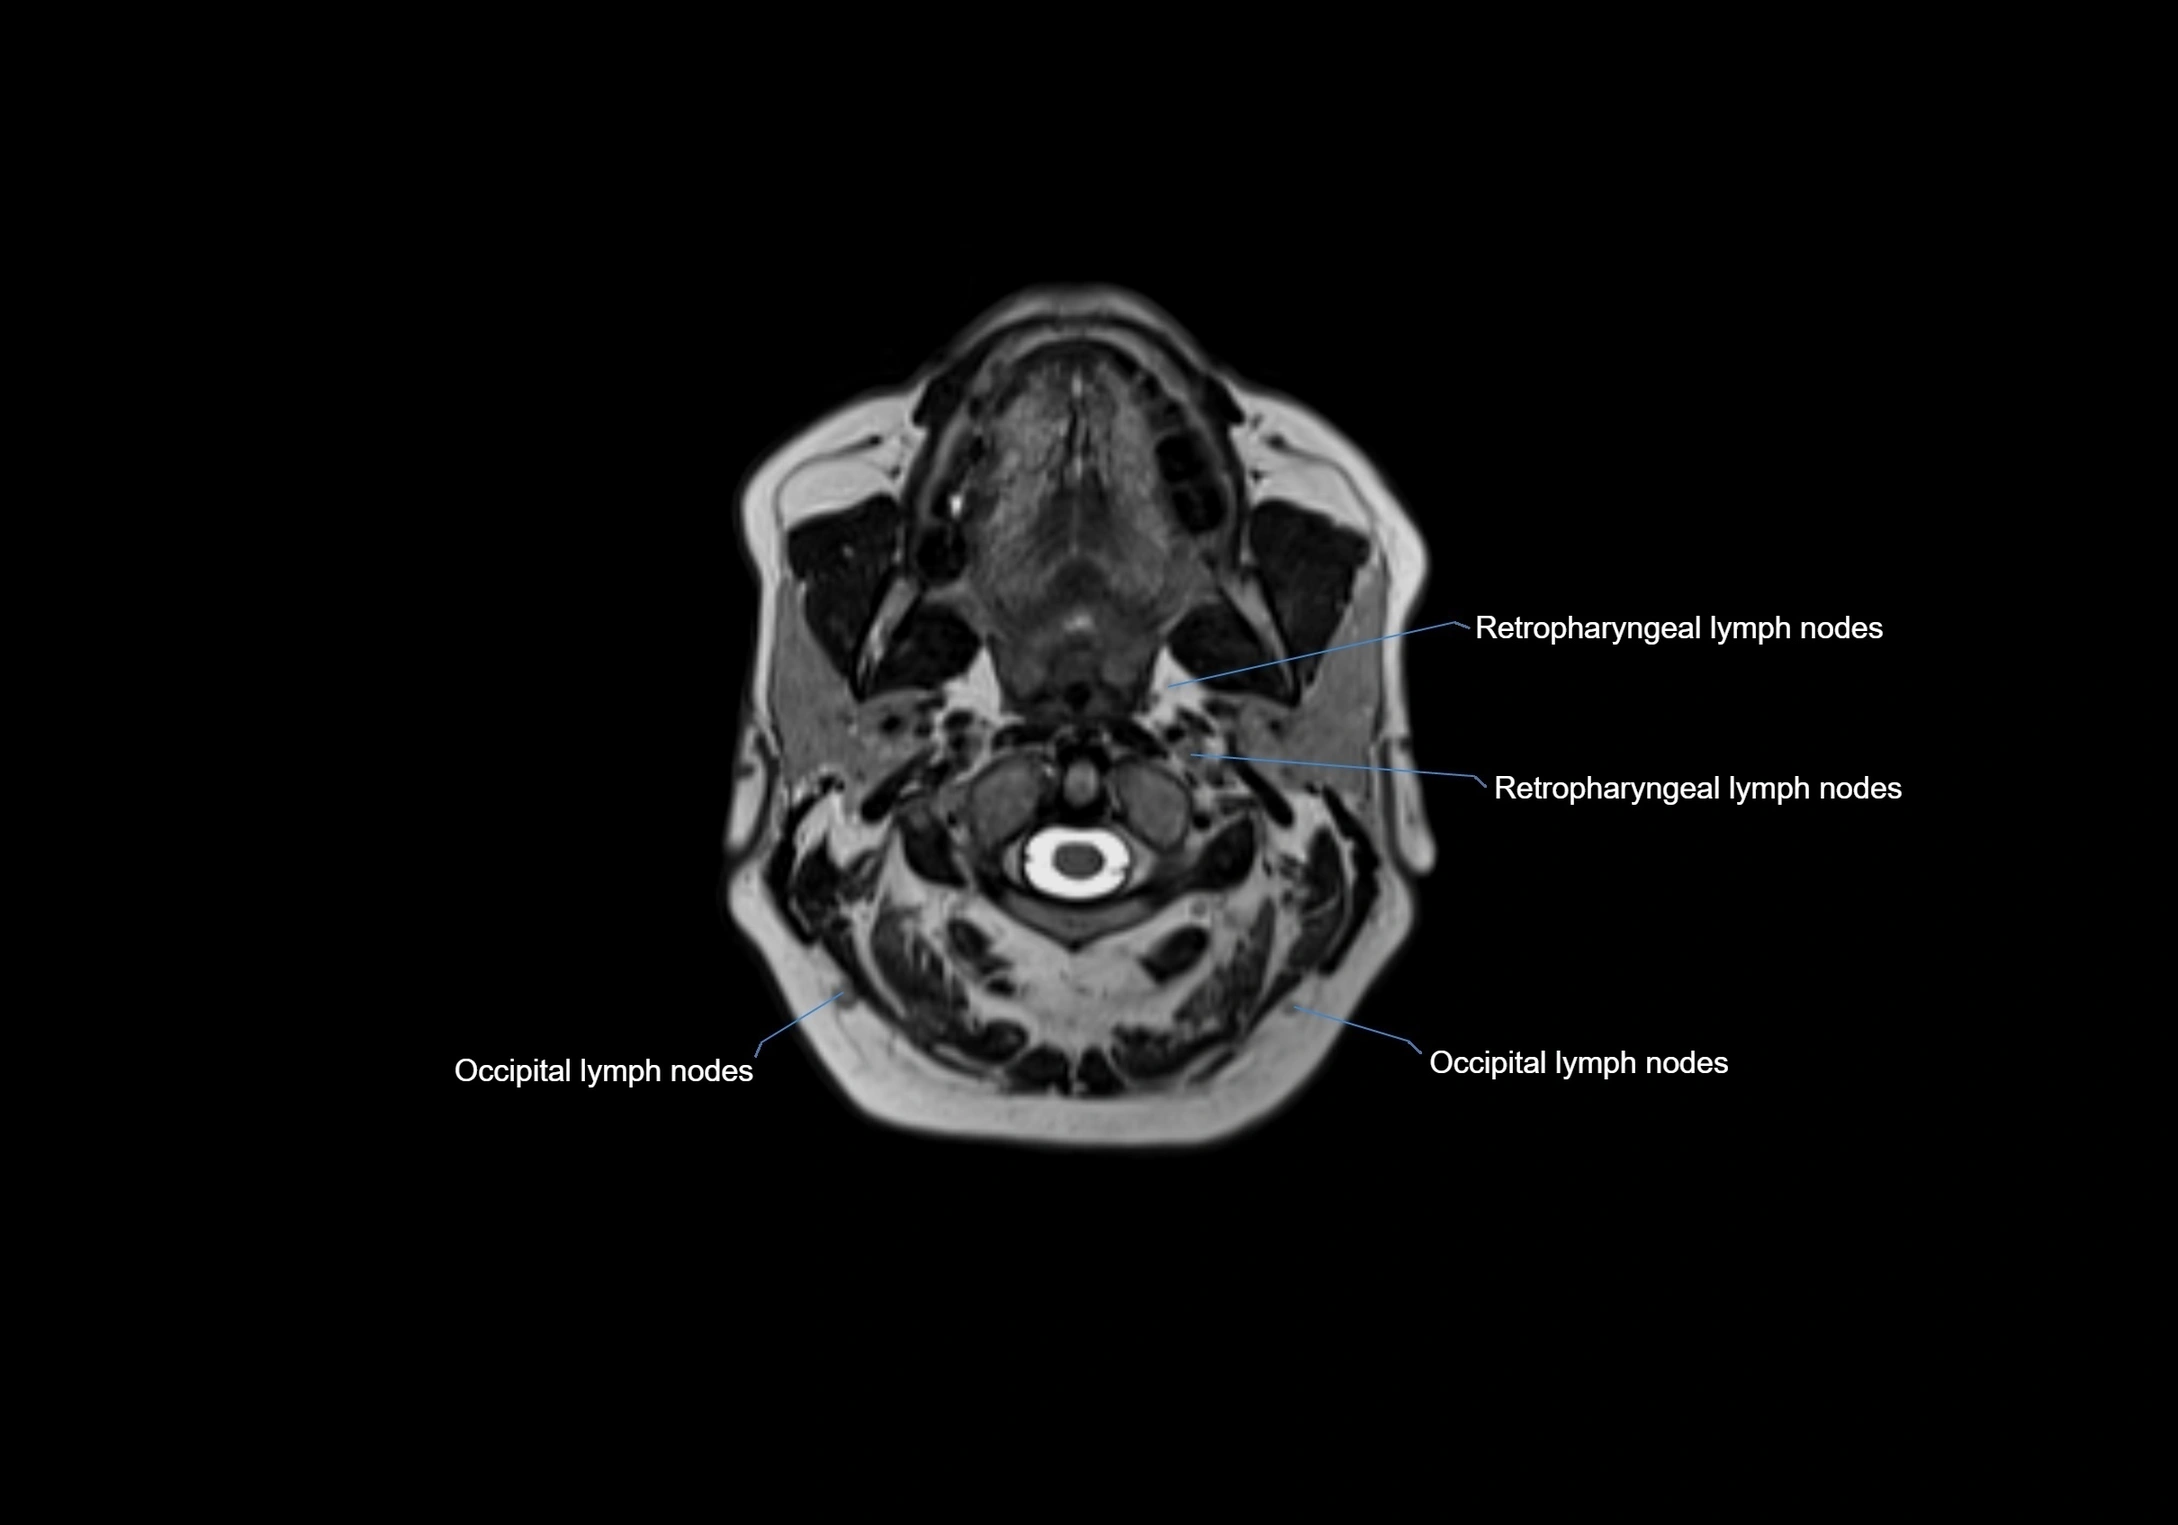

MRI Appearance

T1-weighted images:

• Normal accessory nodes appear as small, oval hypointense to intermediate signal structures within subcutaneous fat

• Surrounded by hyperintense fat, enhancing contrast for visualization

• Pathological nodes may appear enlarged or rounded, sometimes with cortical thickening

T2-weighted images:

• Nodes show intermediate signal, with surrounding fat bright

• Useful for detecting edema, inflammation, or infiltration

• Fatty hilum may appear slightly hyperintense relative to cortex

MRI images

image